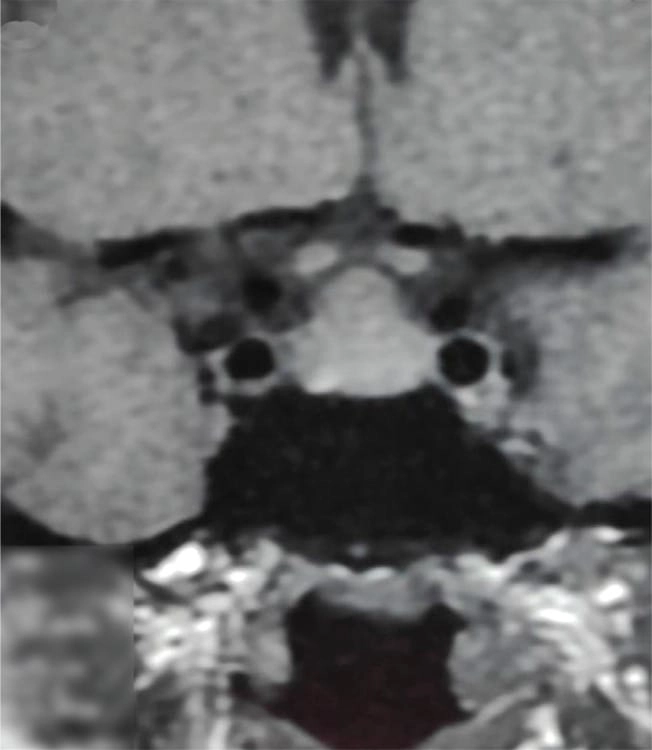

চিকিৎসক তথা আবিষ্কারক সত্যম তিনটি কেসের বিষয় নিয়ে যখন তুলনা করতে নিলেন এবং পুরনো সৃষ্টি ঘাটতে শুরু করলেন তখন তিনি দেখতে পান সবগুলি ক্ষেত্রেই একই রকম সাদৃশ্য অর্থাৎ পিটুইটারি গ্রন্থি মাঝের অংশ এই গ্রন্থি দেখতে খানিকটা প্রজাপতির মতোই এবং তার মাঝের অংশের (প্রজাপতির দেহের উপরের অংশ মাথার মতই দেখতে) উপরের ভাগ সব ক্ষেত্রেই ডোমের মত বা গম্বুজ আকৃতির। তিনি এই ডোম বা গম্বুজ আকৃতি হওয়ার কারণ বিশ্লেষণ করতে গিয়ে দেখেন পিটুইটারির সামনের অংশ যেখানে থাইরোট্রপগুলো থাকে, যেখান থেকে এই টিউমারটি হয়। আর যখনই এটি বাড়বে তখন টমের মতনই তৈরি হবে। অর্থাৎ গম্বুজ আকৃতির। আর সেখান থেকেই ডোম-সাইনের উৎস অর্থাৎ আবিষ্কার।

MRI-তে এই হাইপারপ্লাসিয়া সাধারণত গম্বুজ-আকৃতির ও সমমিত হয় এবং হোমোজেনাস সিগনাল ইন্টেনসিটি দেখায়, যেখানে সাধারণ নন-ফাংশনাল পিটুইটারি অ্যাডেনোমা নানা আকার ও অসমতা নিয়ে দেখা যায়।